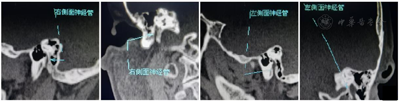

生命体征:体温36.5℃,脉搏70次/min,呼吸18次/min,血压120/80 mmHg。入院MCV测定(用脉冲电流分别刺激左右面神经,于左右眼轮匝肌及口角匝肌记录),左侧记录的神经电位波幅均降低(眼轮匝肌:左3.3 mV,右8.3 mV;口轮匝肌:左1.1 mV,右3.8 mV),提示左侧面神经病变、异常运动传导速度。神经重复刺激结果未见异常。颞骨高分辨CT示左侧面神经管较对侧增宽,局部膨大,最宽径约4.6 mm,双侧乳突气化稍差,左侧乳突黏膜略增厚(图1、图2)。

患者术后一般状态良好,诉睡眠可闭眼,伸舌可自行调整居中,听力无明显改变。术后第7天出院。分别于术后第3个月、6个月、1年、2年、3年随访,影像学检查术后乳突CT平扫+增强提示术后移植段神经在位,生长良好,未见肿瘤复发。面神经功能H-B Ⅲ级,无听力下降(图4)。